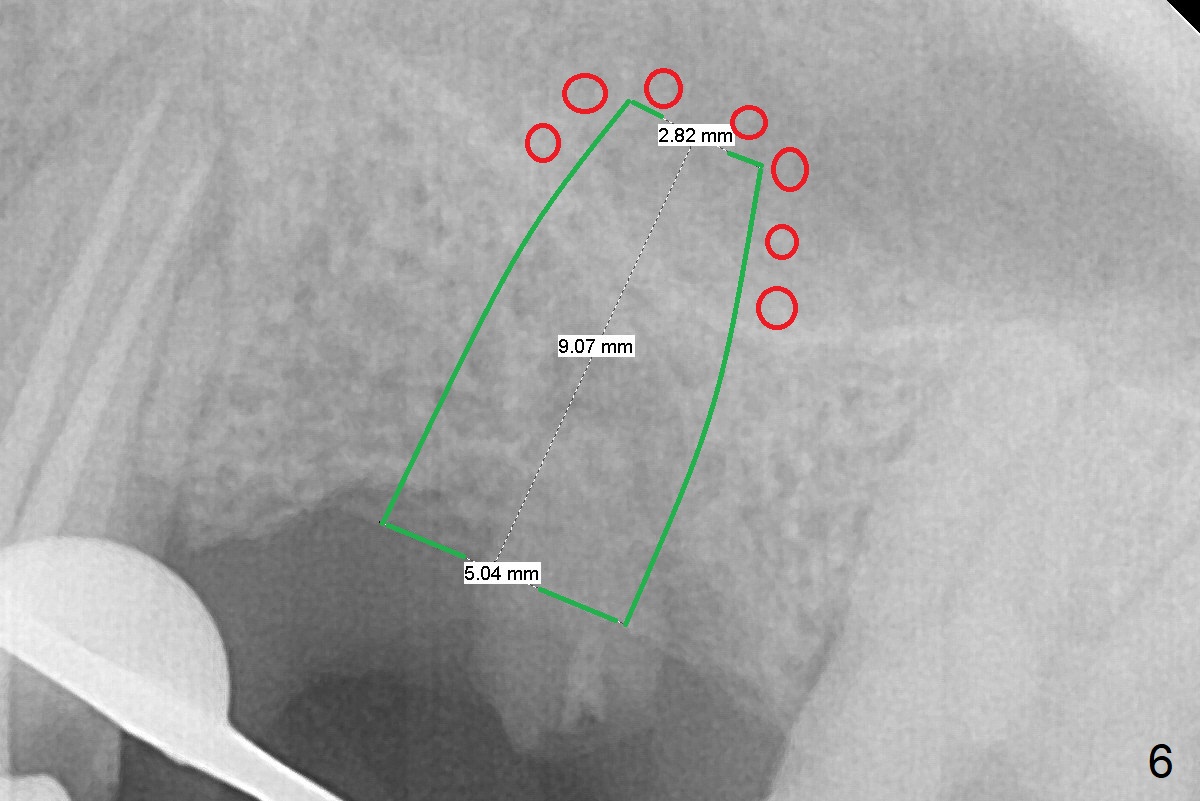

A 37-year-old man will return for #14 extraction and implant after RCT at #13 (Fig.1). After extraction (Fig.2), use Magic Expander (ME) along the long axis of the socket to initiate osteotomy shy of the sinus floor (Fig.3 (<9 mm gingival level)) and change the trajectory at the same time (Fig.4 white arrow). Take the 1st intraop PA when a small ME is stable. Gradually increase the depth for sinus lift as the diameter of MEs increases (Fig.5). Take preop photos to show the residual root and the alveolus (whether it is atrophic or not). Place bone graft (Fig.6 red circles) prior to dummy implant (green).